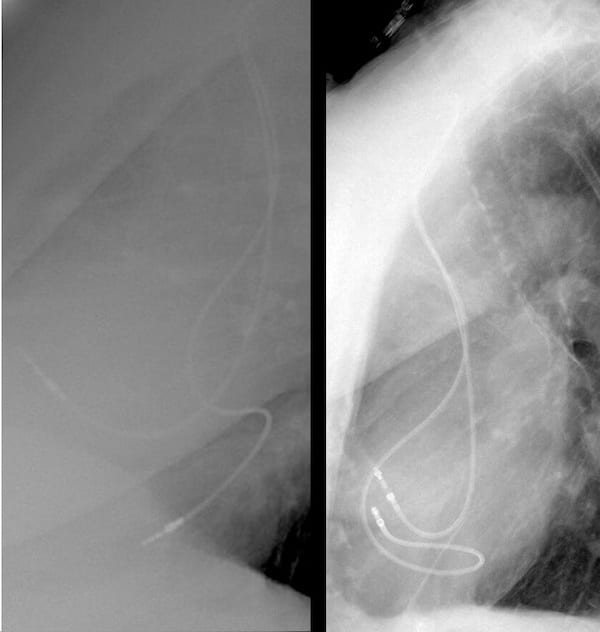

…so how about a lateral CXR?

For many of us the role of the lateral CXR is to localise or investigated pulmonary pathology, and we don’t always look at the cardiac silhouette. In this case an understanding of the lateral cardiac silhouette is essential to confirm our ECG suspected diagnosis.

Looking at this lateral CXR we can see one pacemaker lead sits anteriorly, and the other is sitting posteriorly, this is NOT normal.

On a lateral CXR the right ventricle sits anteriorly with the left ventricle sitting posteriorly.

This CXR confirms ventricular lead placement in the left ventricle.

The following PA and lateral CXR are taken from an unrelated case with appropriately placed pacing leads in the right atrium and right ventricle.

- Note the PA CXR appearance is not too different from the PA CXR in our case of lead misplacement

- Note on the lateral CXR both leads are placed anteriorly signifying right sided placement.